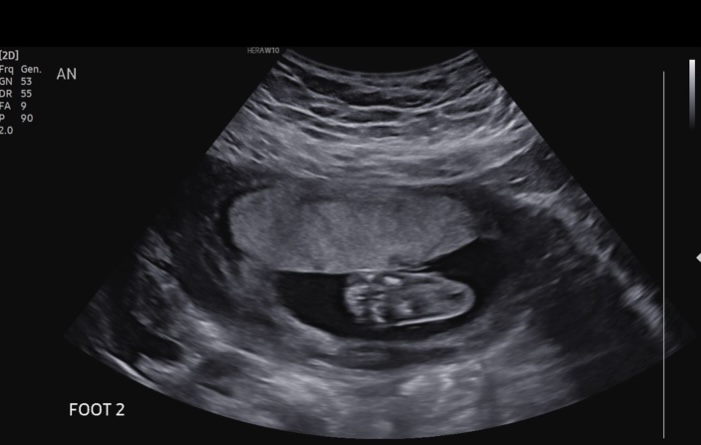

We had our halfway ultrasound and got to see our wiggly little guy! He was moving all over, but then refused to move when the tech needed him to so she could get a better angle. Such a stubborn little boy! Everything is measuring perfectly and all looks great, which is such a relief and we are so grateful! Little guy is moving a LOT now and I can feel him all the time, which makes it much more real that we’re actually having a baby!